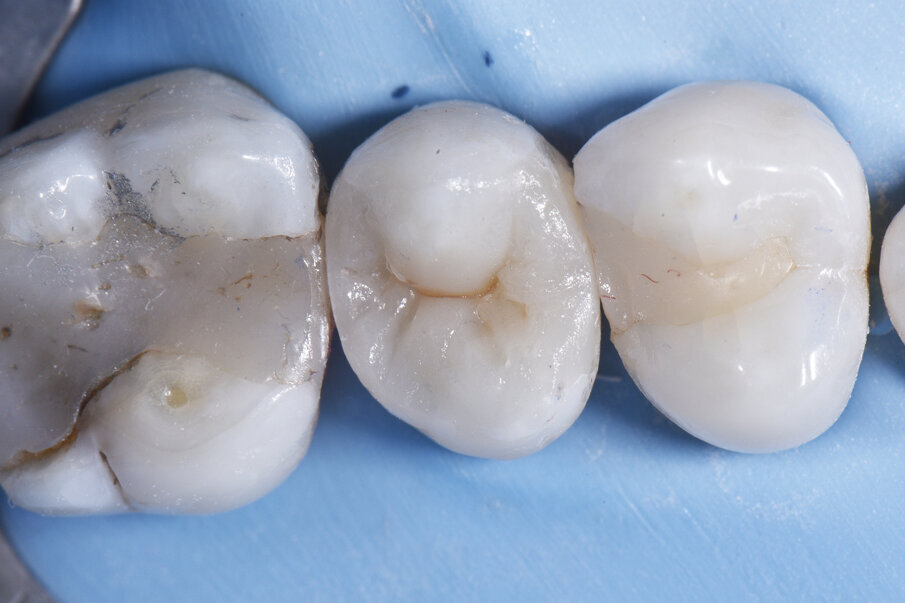

Before - Intraoperative situation showing extent of large MODL Class II restoration. Resin-modified calcium silicate liner placed against area of deeper dentin with near-carious pulp exposure. Wedgeguards will protect against accidental adjacent tooth grazing during preparation, and also double as the wedge for the Palodent® V3 sectional matrix assembly.

A 43 year old female came to my practice with a history of non-attendance. She was concerned about generalised sensitivity with her heavily-restored dentition, many teeth of which featured extensive composite restorations with recurrent caries detectable both clinically and radiographically. Certain teeth with extreme structural compromise were planned for bonded porcelain restorations, however, restorations like this large MOD were planned to be restored with direct composite due to financial constraints.